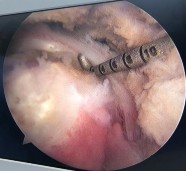

Hình phụ lục 2A: Phim CHT bệnh nhân trước mổ cho thấy rách lớn và co rút gân trên và dưới gai trên phim cắt mặt phẳng trán.

(Nguồn: BN nghiên cứu)